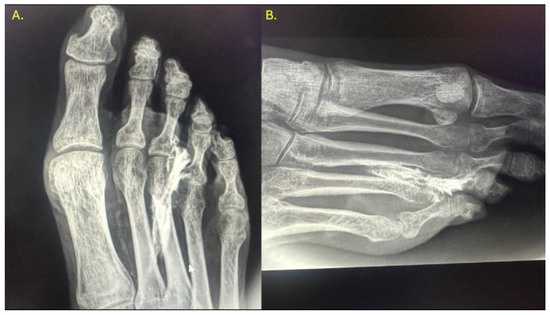

In all intra-articular injections (n = 12), iodinated contrast dispersion remained confined within the articular capsule (Figure 3). Radiographic images revealed a contained, symmetrical pattern with sharply defined margins and an ovoid or triangular morphology, depending on the projection plane. The distribution of contrast was homogeneous in all joints, with no evidence of extravasation into the collateral ligaments, dorsal capsule, or pericapsular regions. These findings support the hypothesis that the MTP joint functions as a closed, sealed cavity, offering a significant anatomical advantage for performing selective and reproducible diagnostic blocks.

Figure 3. Dorsoplantar radiograph of the right forefoot following intra-articular injection of radiopaque contrast. A volume of 0.5 cc was injected into the second metatarsophalangeal joint, 0.4 cc into the third, and 0.3 cc into the fourth. Complete filling of the joint cavities is observed without contrast extravasation, confirming the sealed capsular nature of each articulation.